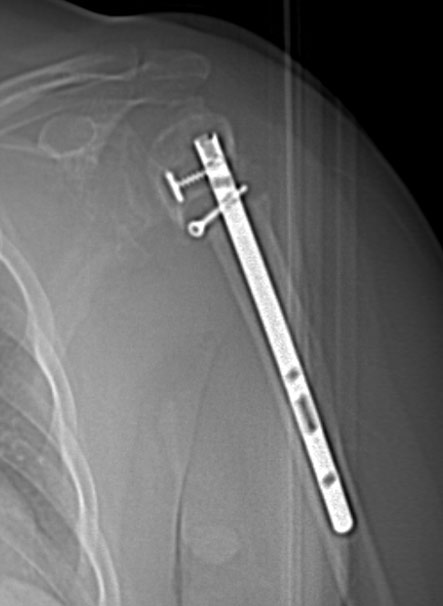

În cazuri speciale, cum sunt prezența de materialele metalice (tije, șuruburi, proteze), ele vor artefacta imaginea puternic, și de aceea atât protocolul de achiziție, cât și cel de postprocesare sunt puțin diferite. Pentru achiziție se vor utiliza parametri electrici cu valori mai mari și slice foarte fin combinat cu un pitch subunitar, eventual cu modificări ale hărții de afișare a nuanțelor de gri (extended CT scale). Din punct de vedere al postprocesării, reconstrucțiile volumetrice cu evidențierea metalului prin transparența osului sunt foarte utile și ușor de înțeles atât de radiolog cât și de ortoped.

Image

Radiografie humerus – material metalic de osteosinteză (tijă)